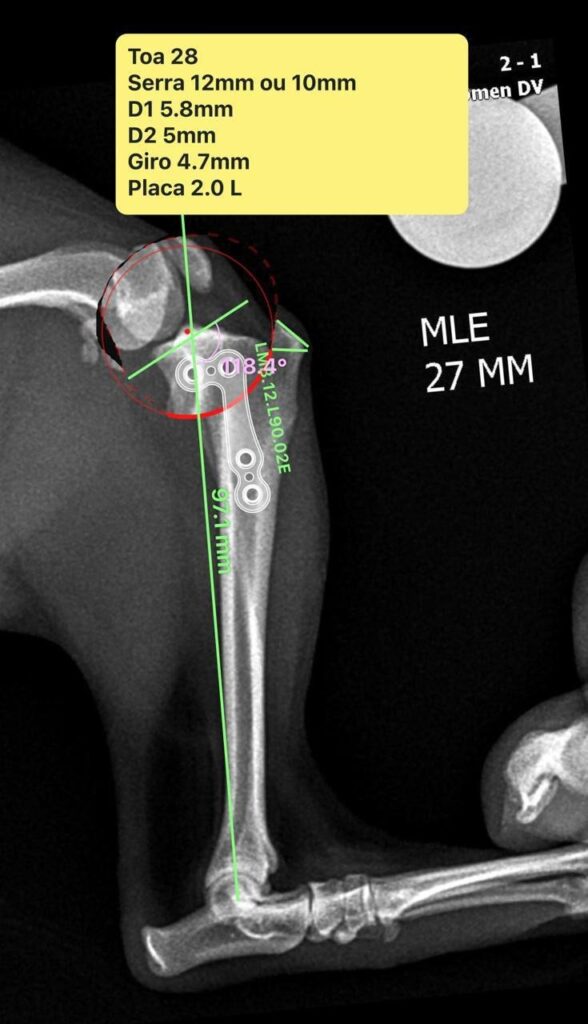

Surgical treatment was selected, consisting of a modified TPLO combined with trochleoplasty to address both conditions. Surgical planning, using a radial TPLO cut, was performed with Vpop Pro® software following the described method for measuring the patellar ligament angle (PLA) relative to the tibial plateau, which was 118.4° (Figure 3).

The measured tibial plateau angle (118.4°) was essential for osteotomy planning, since this parameter directly influences CrCL biomechanical forces (Slocum & Devine, 1983). The modified TPLO, combined with trochleoplasty, aimed to simultaneously correct instability due to CrCL rupture and grade II patellar luxation, with reduced surgical aggressiveness and shorter operative time. Although TPLO is well established for CrCL rupture treatment, its application combined with patellar luxation management remains sparsely documented, emphasizing the relevance of this report.

Figure 3: Preoperative surgical planning. Mediolateral projection showing the measurements, angles, and positioning of the fixation plate to be used during the procedure.